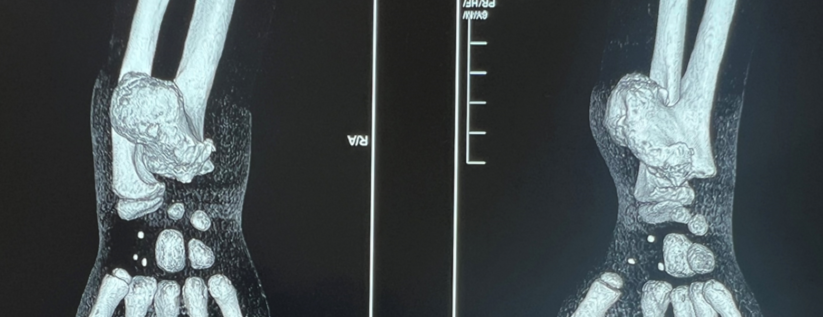

Опухоль по размеру сравнима с объёмом предплечья ребёнка

«У Демида диагностирована остеохондрома дистального метаэпифиза правой локтевой кости, опухоль размером 4×5 см — что сопоставимо с объёмом предплечья ребенка. Часто такое новообразование может появляться в зоне роста кости, и в данном случае затрагивает и зону роста, и эпифиз — и вследствие этого локтевая кость деформирована и отстаёт в размерах.

Хирургическое вмешательство было направлено на полное удаление данного образования.

Новообразование располагалось вблизи локтевой артерии и локтевого нерва, и необходимо было действовать максимально аккуратно, не повреждая мягкие ткани, сосудисто-нервный пучок. В послеоперационном периоде ребенок хорошо себя чувствует, движения в лучезапястном суставе — в полном объёме, поэтому реконструктивных вмешательств на предплечье на данный момент не планируется», — объясняет врач-травматолог-ортопед Дастанбек Абдикапаров.